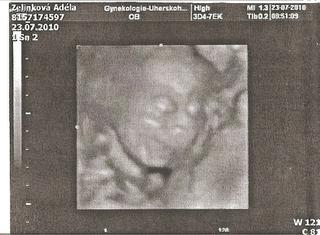

Adeli: ty jsi koza 😀 Vzdyt je vubec krasny, ze se da udelat nejaky obrazek miminka, ts.. Kamoska, netlusta, nemela od miminka nic, protoze ten potvorak si strkal rucicky pred oblicej, celou dobu 😉